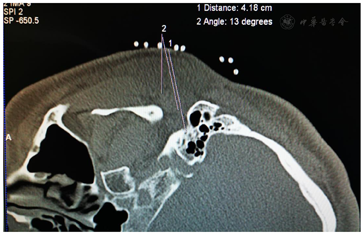

入院后完善相关检查:血常规、尿常规、血沉、凝血全套、前降钙素、梅毒系列+HCV+HIV 、乙肝三系+梅毒系列+HCV+HIV、大便常规+OB、生化分析、肿瘤相关物质测定、肿瘤系列均未见明显异常;术前头颅CT、颅脑MR检查排除了桥脑-小脑角占位病变,使用三维飞行时间磁共振血管造影(3D-TOF MRA)未见双侧面神经根遭受伴行血管压迫(图1)。术前面部表面肌电图可见双侧眼轮匝肌同步收缩和口轮匝肌爆发性放电,未见异常肌电反应(abnormal muscle response,AMR)。

鉴于MS与HFS的临床表现有高度相似之处,我们设想,用于治疗HFS的面神经射频技术有望用治疗MS。经报请医院伦理委员会讨论通过(LS2019-013),决定给患者施行双侧面神经射频治疗。术前向患者及其家属详细交待操作经过和可能出现的轻度面神经麻痹并发症,取得知情同意并签署书面知情同意书后,嘱患者右侧向上侧卧于CT台上,安置血压、心电图、脉搏血氧饱和度监测设施并给予鼻导管吸氧,并在耳垂前后放置CT定位定位栅(图2)。用鼻旁窦模式拍摄头颅定位像,并对乳突区进行层厚3 mm轴位扫描,选取含茎乳孔且无颞骨鼓部骨质阻挡的CT层面作为穿刺层面,并在该层面上设计穿刺路径:以右侧茎乳孔为穿刺靶点,用CT自带测量工具软件由右茎乳孔向前上拉直线,该线与皮肤的交点即为穿刺点,测量穿刺深度(穿刺点至靶点的距离)和穿刺角度(穿刺路线与矢状面的夹角)(图3)。对穿刺点进行局部麻醉,用长度为10 cm、裸露端为5 mm的7号射频针在CT引导下穿刺至靶点(图4)并CT扫描三维重建观察确认(图5),随后用低频(2 Hz)电流进行运动神经刺激测试,0.5 mA电流电刺激即能诱发出右侧面肌出现与电刺激相同频率痉挛性抽动,见视频,给予65℃标准射频消融,同时嘱患者鼓腮、闭眼,射频第27秒鼓腮漏气,右眼不能紧闭,即停止射频,结束手术,见视频。2 d后同样于CT引导下行左侧茎乳孔穿刺面神经射频消融治疗(图6,图7,图8)。